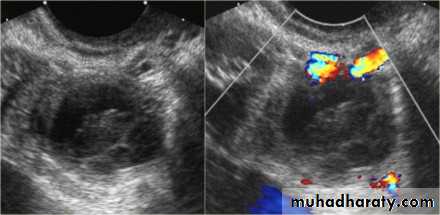

Blighted ovum

Anembryonic pregnancy is a form of a failed early pregnancy, where a gestational sac develops, but the embryo does not form. The term blighted ovum is synonymous with this, but is falling out of favour and is best avoided.

Radiographic features

Ultrasound

An anembryonic pregnancy may be diagnosed when there is no fetal pole identified on endovaginal scanning , and:

the size of the gestational sac is such that a fetal pole should be seen: MSD ≥25 mm on TVS (by RCOG criteria)